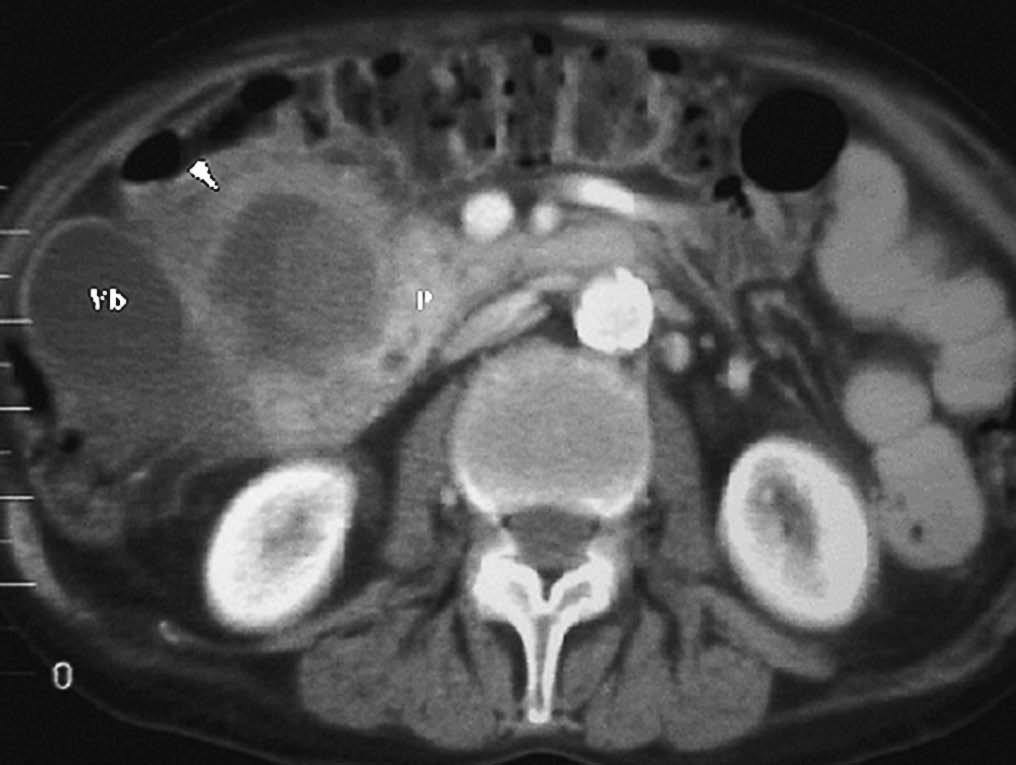

La colecistitis también puede afectar al duodeno, produciendo un engrosamiento de pared secundario a la extensión de la inflamación vesicular. Dicha inflamación puede provocar un absceso de pared duodenal (fig. 13). La existencia de un nivel hidroaéreo en la TC sugiere que se ha producido una comunicación con la luz intestinal. La inflamación puede progresar y perforar la pared duodenal ocasionando una fístula bilioduodenal, identificándose en la ecografía como un trayecto hipoecoico con paso de contenido ecogénico (gas) entre vesícula y duodeno. También se puede observar la presencia de aire en vesícula, que puede extenderse al resto de la vía biliar (neumobilia) (fig. 14). La salida de la colelitiasis a través de la fístula y su impactación en el tracto intestinal puede producir un íleo biliar20.

Fig. 13--Absceso en pared duodenal secundario a colecistitis. Tomografía computarizada con contraste intravenoso. Colección hipodensa (flecha) en contacto con la pared de la segunda porción duodenal, en proximidad a una vesícula con las paredes engrosadas (Vb).